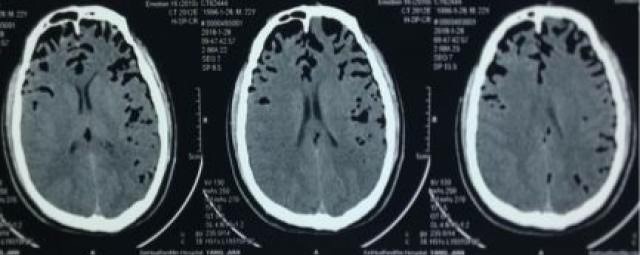

神经内科和脑外科在一层楼上,一天唐文碰到了他的主治医生陈灿,陈灿问起他的病情,唐文详细的说了一遍,陈灿感觉不妙,担心清鼻涕是脑脊液鼻瘘,建议他马上做个CT,并给他开具了检查单,检查结果不出所料(见下图)。

唐文颅内有大量气体,颅底若有骨质破坏,脑膜破损,不仅会有脑脊液从硬脑膜渗出,当患者用力排便、剧烈运动(包括性生活)等,还可以有大量气体进入颅内,出现头痛、恶心呕吐、脑脊液漏。